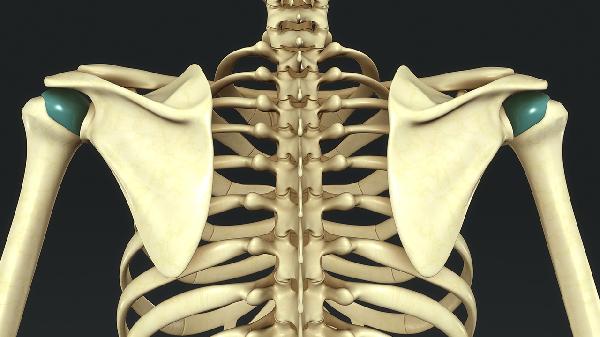

直徑小于10毫米的靜止性骨瘤通常無需干預(yù)。上頜竇骨瘤多為良性骨性增生,微小骨瘤常在影像檢查中偶然發(fā)現(xiàn),若無占位效應(yīng)或壓迫癥狀,臨床建議定期觀察,每6-12個(gè)月復(fù)查鼻竇CT評(píng)估變化。

年增長超過2毫米建議手術(shù)干預(yù)??焖偕L的骨瘤需排除骨化纖維瘤等病變,通過連續(xù)影像對(duì)比確認(rèn)生長速度,若壓迫鄰近眼眶或顱底結(jié)構(gòu),需耳鼻喉科聯(lián)合口腔頜面外科會(huì)診。

骨瘤導(dǎo)致竇腔引流障礙需手術(shù)切除。當(dāng)骨瘤占據(jù)上頜竇腔50%以上容積,或?qū)е吗ひ耗夷[形成時(shí),可采用鼻內(nèi)鏡下微創(chuàng)手術(shù),術(shù)中配合導(dǎo)航系統(tǒng)精準(zhǔn)切除。